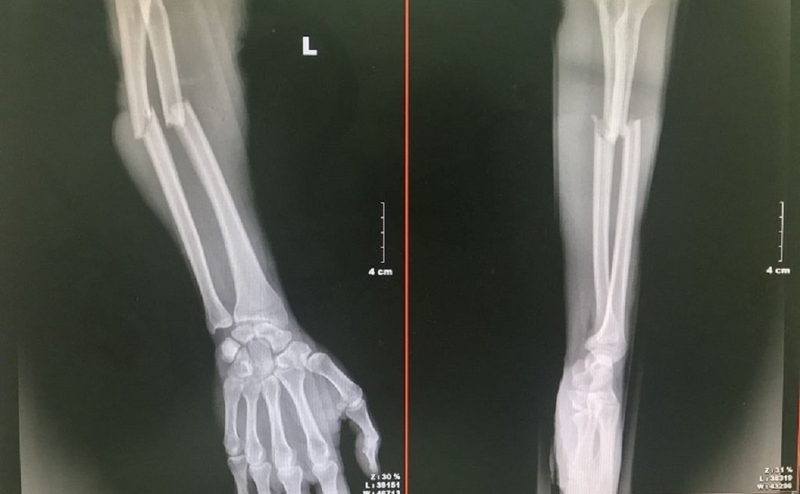

Trong phần cẳng tay, có hai loại xương dài đó là xương trụ và xương quay. Vậy vị trí của xương xương trụ và xương quay ở đâu?

Còn xương trụ nằm ở phía trong và gần cơ thể, tiếp giáp với xương cổ tay phía trên và xương cánh tay phía dưới thông qua đĩa sụn.

Về cấu tạo thì xương trụ bao gồm hai đầu và một thân xương. Cụ thể như sau:

Hai đầu: Đầu trên chia thành 2 mỏm và 2 khuyết, trong khi đầu dưới có chỏm xương. Mỏm khuỷu có cấu trúc hình tháp với bốn mặt trước, trên, trong, ngoài, nổi rõ khi cánh tay được gập. Mỏm vẹt nhô ra phía trước và lắp vào hố mỏm vẹt trong tư thế gập cẳng tay.

Khuyết ròng rọc được tạo ra từ mặt trên của mỏm vẹt và mặt dưới của mỏm khuỷu, có hình bán nguyệt để ăn khớp với ròng rọc của xương cánh tay. Khuyết quay ở mặt bên ngoài mỏm vẹt, khớp với xương quay tại vành đai quay. Chỏm xương ở đầu dưới tạo sự ăn khớp với xương quay qua khuyết trụ.

Thân xương: Hình lăng trụ tam giác với ba mặt và ba bờ. Đặc biệt nó có một cạnh sắc tại thân xương.

Về chức năng thì xương trụ cùng với xương quay đóng góp vào việc tạo thành khớp khuỷu và khớp cổ tay, làm cho cổ tay trở nên linh hoạt hơn.